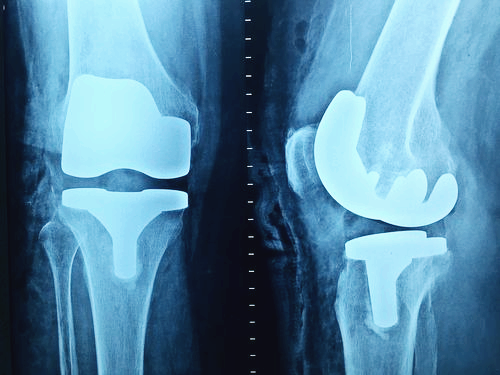

그렇지만 이미 연골의 손상이 심각하다면 관절 영양제를 먹어도 손상된 연골을 복구할 수는 없습니다. 다만 관절의 손상 속도를 지연시키는 보조제 역할 정도로 활용할 수 있습니다.